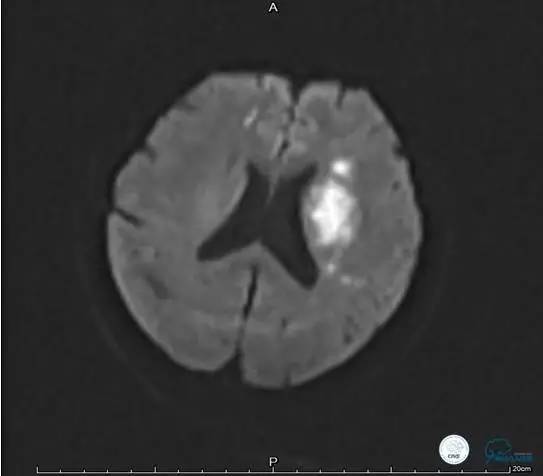

病例5

患者:49岁男性,左侧偏瘫1个月,药物治疗、康复训练效果不好,转我院,肌力0~1级。

core-clilnical明显不匹配,是介入开通的合适患者。

造影评价血管、判断闭塞段,微导丝小心穿过闭塞段,微导管造影,交换技术,球囊扩张,Enterprise支架。在后扩张时导丝刺破M3段血管,蛛网膜下腔出血(SAH)。

微导管进入破裂血管,栓塞弹簧圈1枚,出血停止,结束手术。继续双抗,术后2天肌力2级,神经功能恢复明显加快。

术后即刻和6天后CT,患者无明显临床症状。

半年后复查造影,无支架内再狭窄,可见弹簧圈,患者恢复至自己柱杖行走。